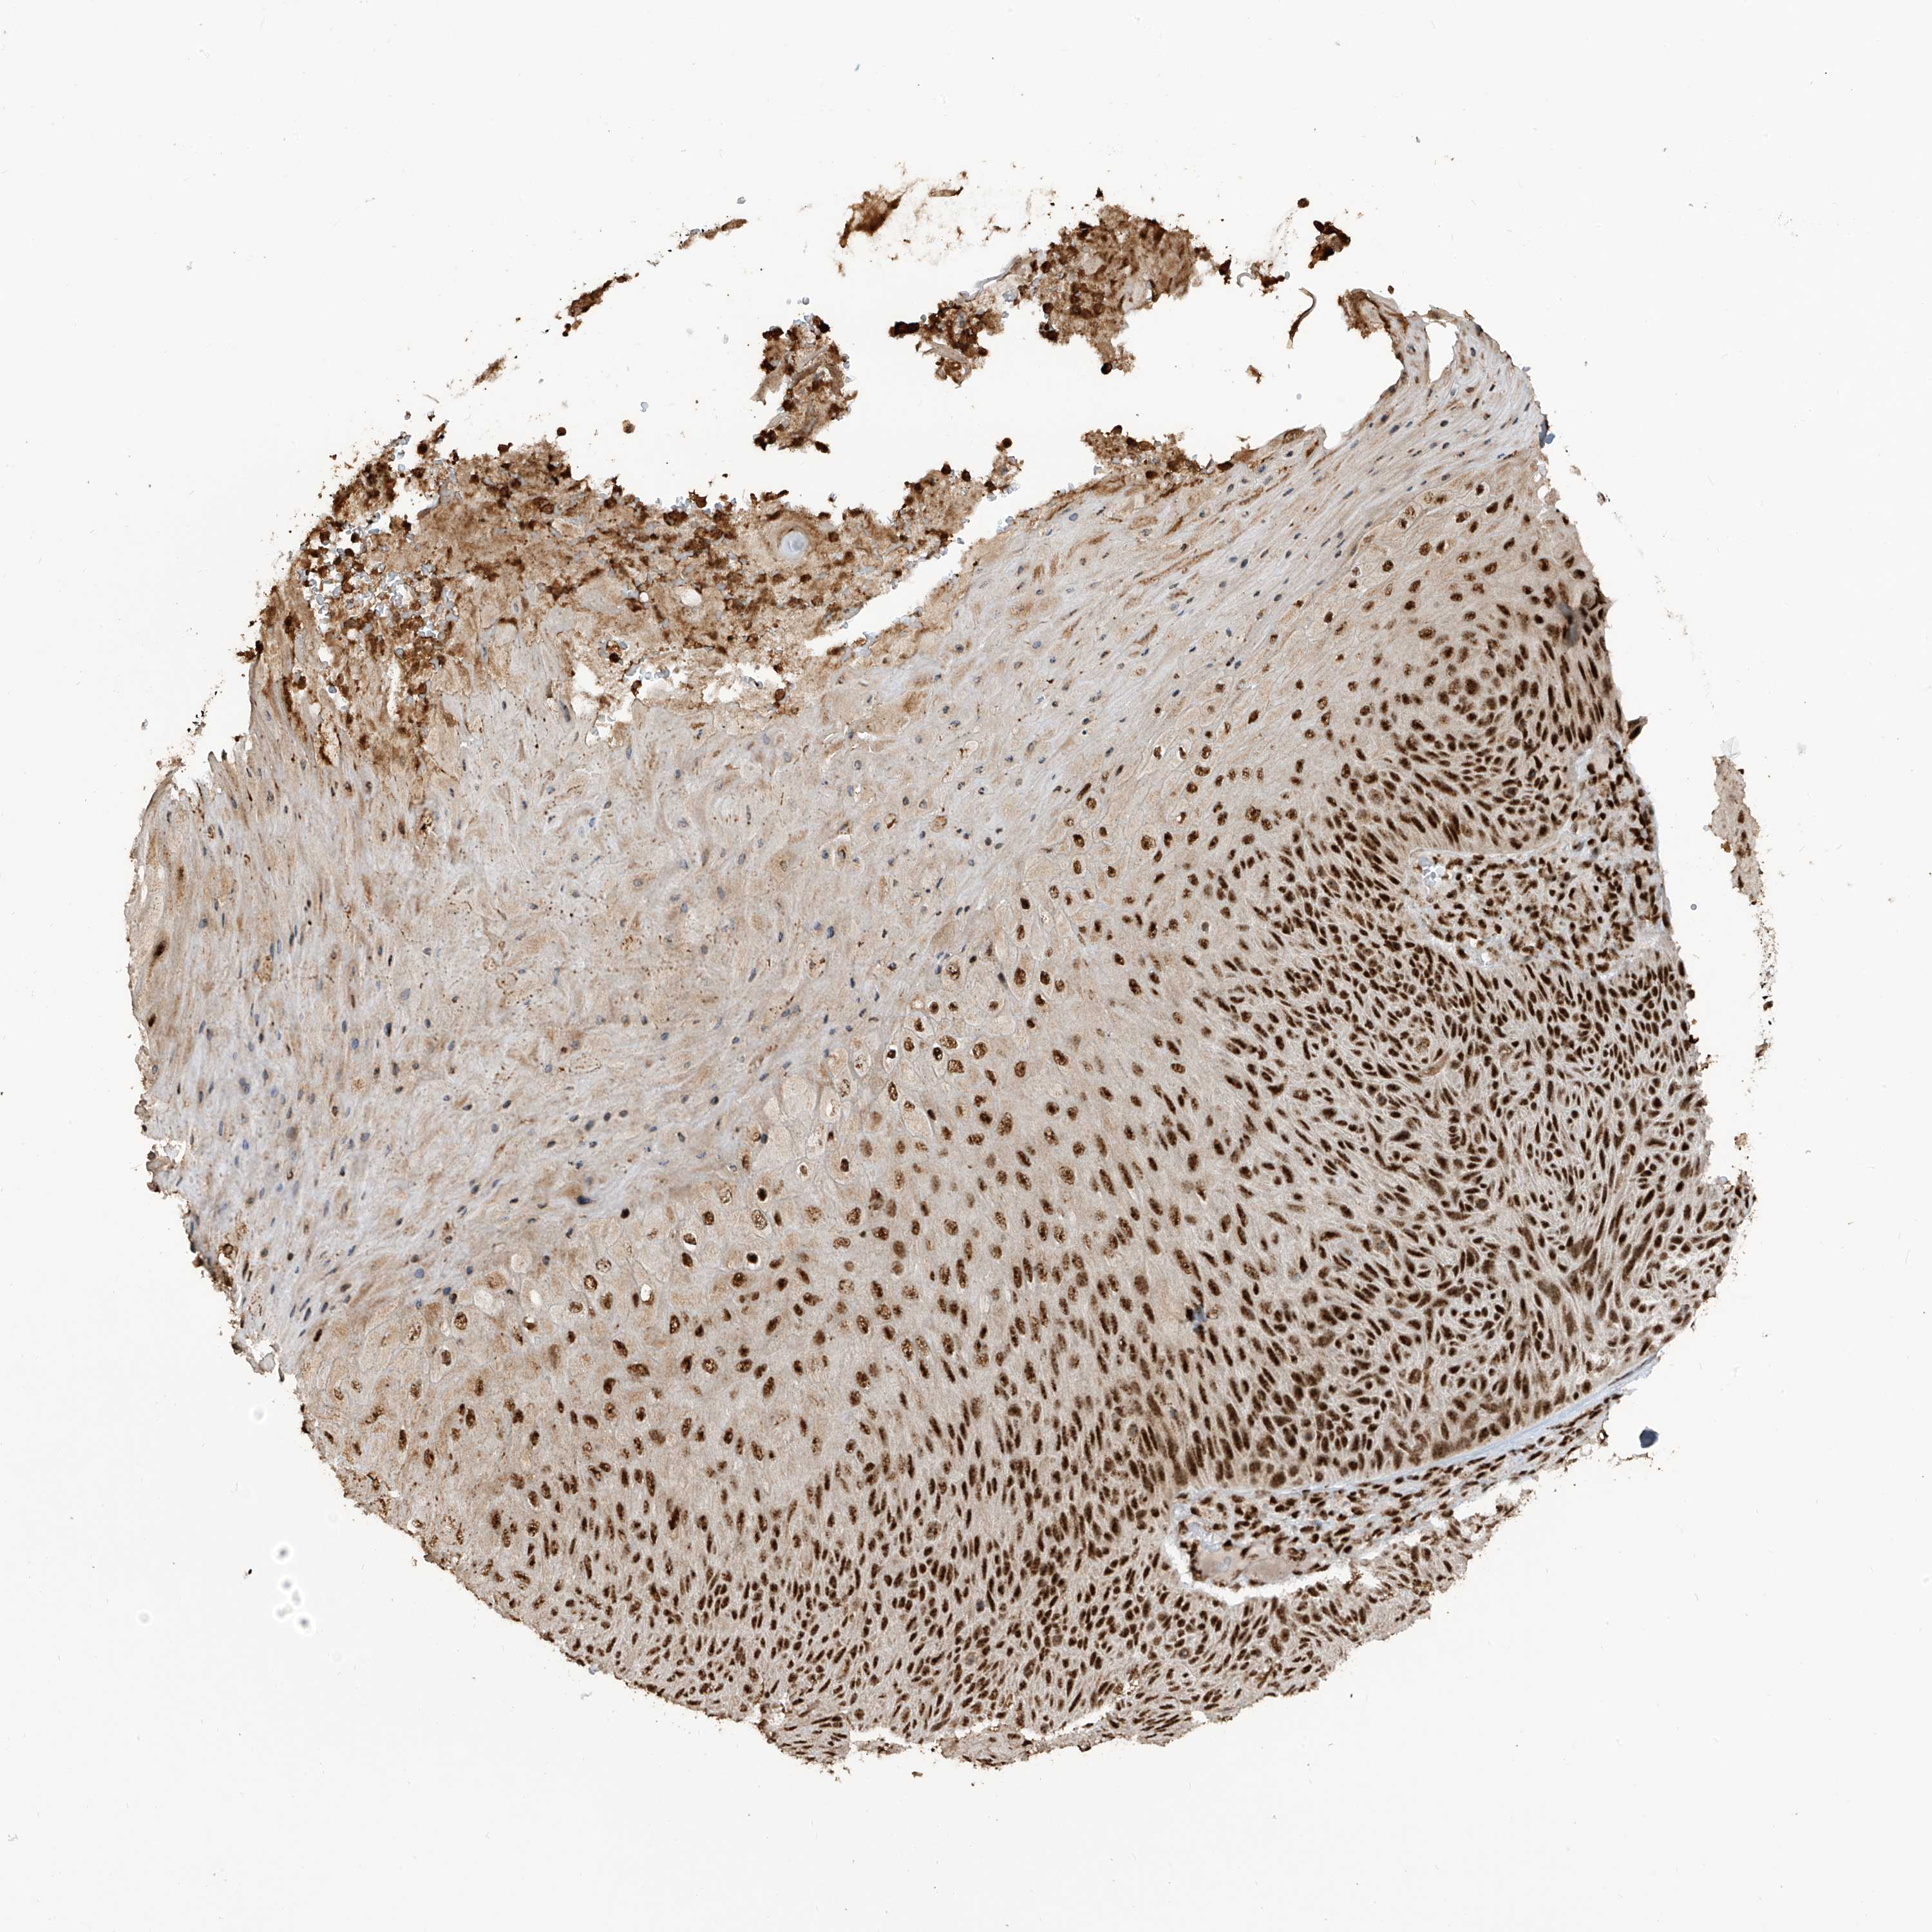

SKIN CANCER - Protein expressioni

A mouse-over function shows sample information and annotation data. Click on an image to view it in a full screen mode. Samples can be filtered based on level of antibody staining by selecting one or several of the following categories: high, medium, low and not detected. The assay and annotation is described here.

Each image is clickable and will lead to virtual microscopy that enables deeper exploration of all samples and also displays staining intensity scores, fraction scores and subcellular localization as well as patient and tissue information for each sample.

Antibody HPA034669

Staining

Medium

Intensity

Moderate

Quantity

75%-25%

Location

Nuclear

Squamous cell carcinoma, metastatic, NOS

Squamous cell carcinoma, NOS